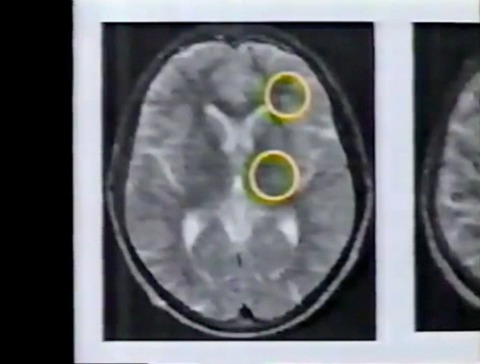

脳の状態に問題はないのか。MRIという画像診断装置を使って、詳しい検査を受けます。

その結果、脳に異常が発見されました。

前頭葉と呼ばれる、脳の前の部分に白い塊があります。神経細胞が死滅したあとです。前頭葉は、計算や思考など、創造的な働きを担う中枢です。ウラジミルさんの知的障害の原因は、ここにあるのではないかと医師たちは考えています。

脳の更に深い部分にも、神経細胞が死滅したあとがありました。ウラジミルさんの疲労感や脱力感の原因は、これではないかと診断されました。